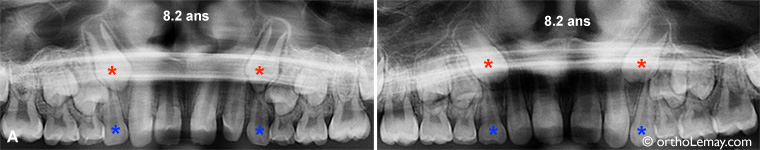

8.2 ans

Ces 2 patients de 8 ans présentent une position des canines permanentes (* rouges) qui peut être favorablement influencée par des extractions sélectives (canines temporaires * bleus).